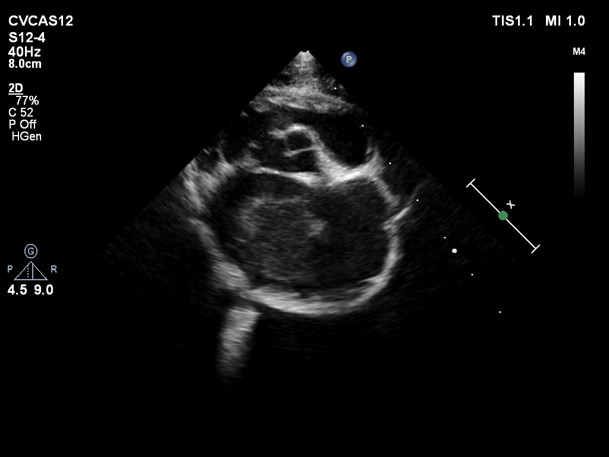

Image (Echocardiogram showing large clot in left atrium of heart).

Feline Arterial Thromboembolism, or FATE, is one of the most serious consequences of cardiac disease in cats. When a cat has advanced cardiomyopathy (heart disease), the left atrium in their heart can become enlarged, which results in decreased blood flow in that area.

Blood clots, also known as emboli, can then form and break loose, entering the body’s circulatory system and causing blockage of blood flow to the cat’s limbs, other organs, or brain. Most commonly, the blood clot will exit the heart, travel

down the aorta (the body’s main artery), and lodge in the iliac arteries (the body’s main blood supply to the hind end), resulting in complete blockage of blood flow to the cat’s rear legs.